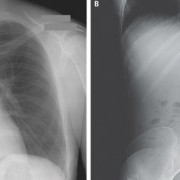

Можеби понекогаш се чувствувате виновно заради обилниот ручек што сте го изеле, но кога ќе видите што ставиле овие луѓе во својот стомак, ќе сфатите дека вие немате причина да се грижите. Барем не сте изеле батерии. Иако можеби имаат помалку калории, попрво би јаделе вкусни слатки со многу масти отколку киселински раствор. Луѓето имаат изедено некои многу чудни нешта…

Батерии